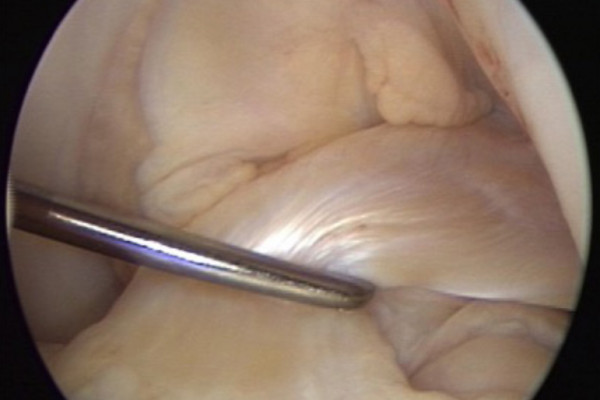

Rekonstruktion des vorderen Kreuzbandes/ Stumpferhaltende Kreuzbandplastik

Kann nach einem Riss des Kreuzbands nicht erhalten werden wird eine sogenannte Kreuzbandplastik durchgeführt. Hierbei wird das Kreuzband durch eine körpereigene Sehne ersetzt. Verwendet wird in der Regel eine Sehne aus dem Oberschenkel. Der Ersatz des Kreuzbandes mittels künstlicher Bänder aus Kohlefaser oder Gore-Text hat sich nicht bewährt. Auch die Verwendung von Spendersehnen führt zu deutlich schlechteren Ergebnissen und ist mit einer erhöhten Wahrscheinlichkeit einer erneuten Instabilität verbunden. Diese Technik kommt daher nur in Ausnahmefällen zum Einsatz. Auch wenn das vordere Kreuzband ersetzt wird so wird der verbliebene Kreuzbandstumpf erhalten, um eine möglichst gute Einheilung zu ermöglichen. Das Eindringen von Gelenkflüssigkeit in die zur Verankerung verwendeten Knochenkanäle wird hierdurch verhindert. Gleichzeitig können Nervenzellen die zur Steuerung des Kniegelenkes beitragen leichter in das Transplantat einwandern.

Zur Durchführung dieses Eingriffes ist lediglich eine Kniegelenksspiegelung und keine langstreckige Eröffnung des Kniegelenkes erforderlich.

Die entnommene Sehne wird mehrfach gefaltet und mit sich selbst vernäht. Zur Fixierung werden Knochenkanäle in den Unterschenkel und Oberschenkelknochen gebohrt. Hierbei ist die Kenntnis der genauen Ansatzpunkte des vorderen Kreuzbandes von entscheidender Bedeutung für ein optimales Operationsergebnis. Die Sehne wird im Rahmen der Kniegelenksspiegelung in die Knochentunnel eingezogen und mittels Titanankern bzw. sich selbst auflösenden Schrauben fixiert.